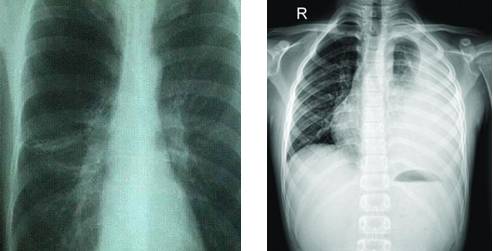

根据美国放射协会和妇产协会的数据,孕妇接受单次胸部X线检查腹中胎儿受到的照射剂量为0.02–0.07毫rad。记住,高于5000毫rad才会造成胎儿损伤,也就是说要至少连续拍5000÷0.02=250000张或5000÷0.07=71428张胸部平片才可能造成胎儿损伤。单次腹部X线平片胎儿受到的照射量为100毫rad(5000÷100=50次),肾盂静脉造影胎儿受到的照射量可能大于1 rad(1000毫rad)。

头胸部CT检查胎儿受到的照射量小于1 rad。

也就是说,普通X线平片通常只会暴露胎儿于非常小的照射剂量。而且通常孕期需要做X线检查时候,孕妇的腹部是会用含有铅的防护衣保护起来的,更进一步降低受照剂量,其实基本是0辐射。除开钡灌肠和小肠连续成像,绝大多数造影剂荧光检查也只会给胎儿带来毫rad的剂量。CT造成的照射依照射数量和成片距离会有不同。盆腔CT可能会给胎儿带来高达1.5 rad的照射,但放射科医生通过使用低剂量技术是可以将它降低到接近250毫rad的(相当于5000÷250=20次CT扫描的剂量),但是CT医师是不会像疯子一样连续同一个部位扫20次的。

常规齿科X线检查,头部X线检查,四肢X线检查,以及胸部X线检查,包括乳腺钼靶检查,或者头胸部CT是不会对胎儿造成损伤的,儿童期癌症的风险提高也可以忽略不计。需要做腹部检查时请与医生商量。